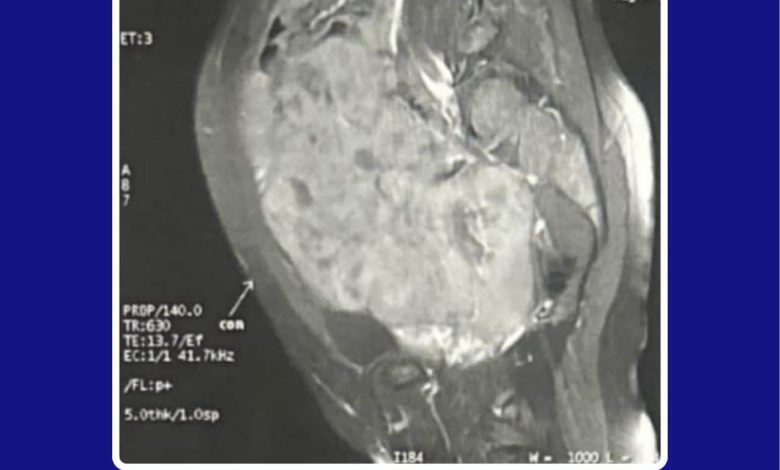

من جانبه، قال الدكتور محمد حنتيرة، إن المستشفى استقبل الطفلة وهي تعاني من آلام حادة وزيادة كبيرة في محيط البطن، حيث تم إجراء كافة الفحوصات اللازمة التي كشفت عن وجود ورم يزن 2 كجم ويمتد ليشمل معظم منطقة البطن والحوض، مما استوجب تدخلاً جراحياً عاجلاً داخل غرف العمليات المجهزة بأحدث النظم العالمية والمخصصة لأورام الأطفال، لضمان استئصال الورم بدقة وكفاءة عالية.